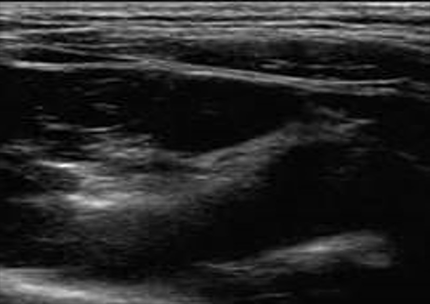

超声波使用高频声波来可视化身体的内部结构。可以使用特殊技术来检测和测量血管中的血流量和组织的材料特性。